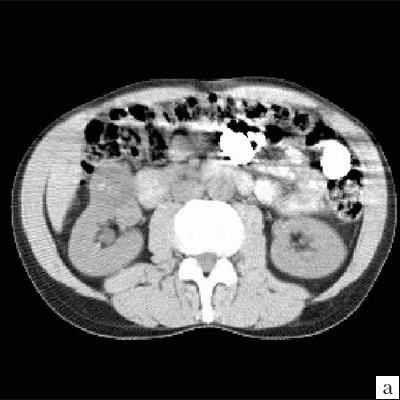

а) До внутривенного контрастирования определяется негомогенное образование неправильной округлой формы с капсулой и едва заметными перегородками, плотность ниже, чем плотность паренхимы почки.

б) После контрастирования отчетливо выявляются плотная стенка и множество перегородок.

а) До внутривенного контрастирования определяется негомогенное образование округлой формы, с единичным кальцинатом, плотность ниже, чем плотность паренхимы почки.

б) После контрастирования (паренхиматозная фаза) отчетливо выявляются плотная стенка и множество перегородок.